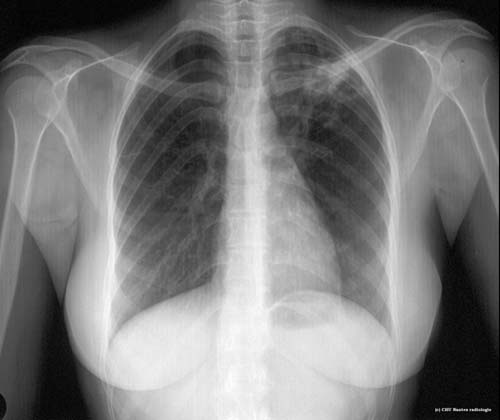

Lésions cavitaires